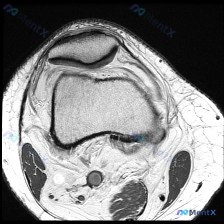

踝关节MRI看软骨异常:这个距骨的信号改变容易漏诊吗?

看到一张踝关节MRI矢状位T1加权影像,问题是观察软骨异常,整理一下读片和分析思路分享给大家。

这是踝关节MRI矢状位T1加权序列,用于评估踝关节及足部解剖结构,先给大家整理读片基础发现:

- 骨骼结构:胫骨远端关节面形态正常,皮质连续,未见明确骨折;足舟骨、骰骨、跟骨骨质轮廓完整,无明显骨折征象;距骨体部上方(距骨穹窿关节软骨下)可见明显局限性低信号异常区,正常T1加权像骨髓应为高信号,这个表现是肯定异常的。

- 关节结构:胫距关节间隙尚可,关节面可见低信号软骨层,但距骨穹窿处软骨下信号异常,提示局部软骨或软骨下骨病变;关节腔内未见显著异常积液信号。

- 软组织与肌腱:跟腱走行清晰,信号均匀连续,无增粗撕裂;足底筋膜走行清晰,无肥厚或断裂。

正常T1加权像骨髓因为脂肪含量应该是中高信号,这个距骨穹窿的局限性低信号,结合软骨异常的提问,我们一步步拆解:

这个病变有几个特点:① 位置正好在距骨穹窿的承重撞击区;② 病灶是局限性的,边界相对清晰;③ 没有广泛的骨髓水肿、骨膜反应,也没有明显关节积液、滑膜增生。